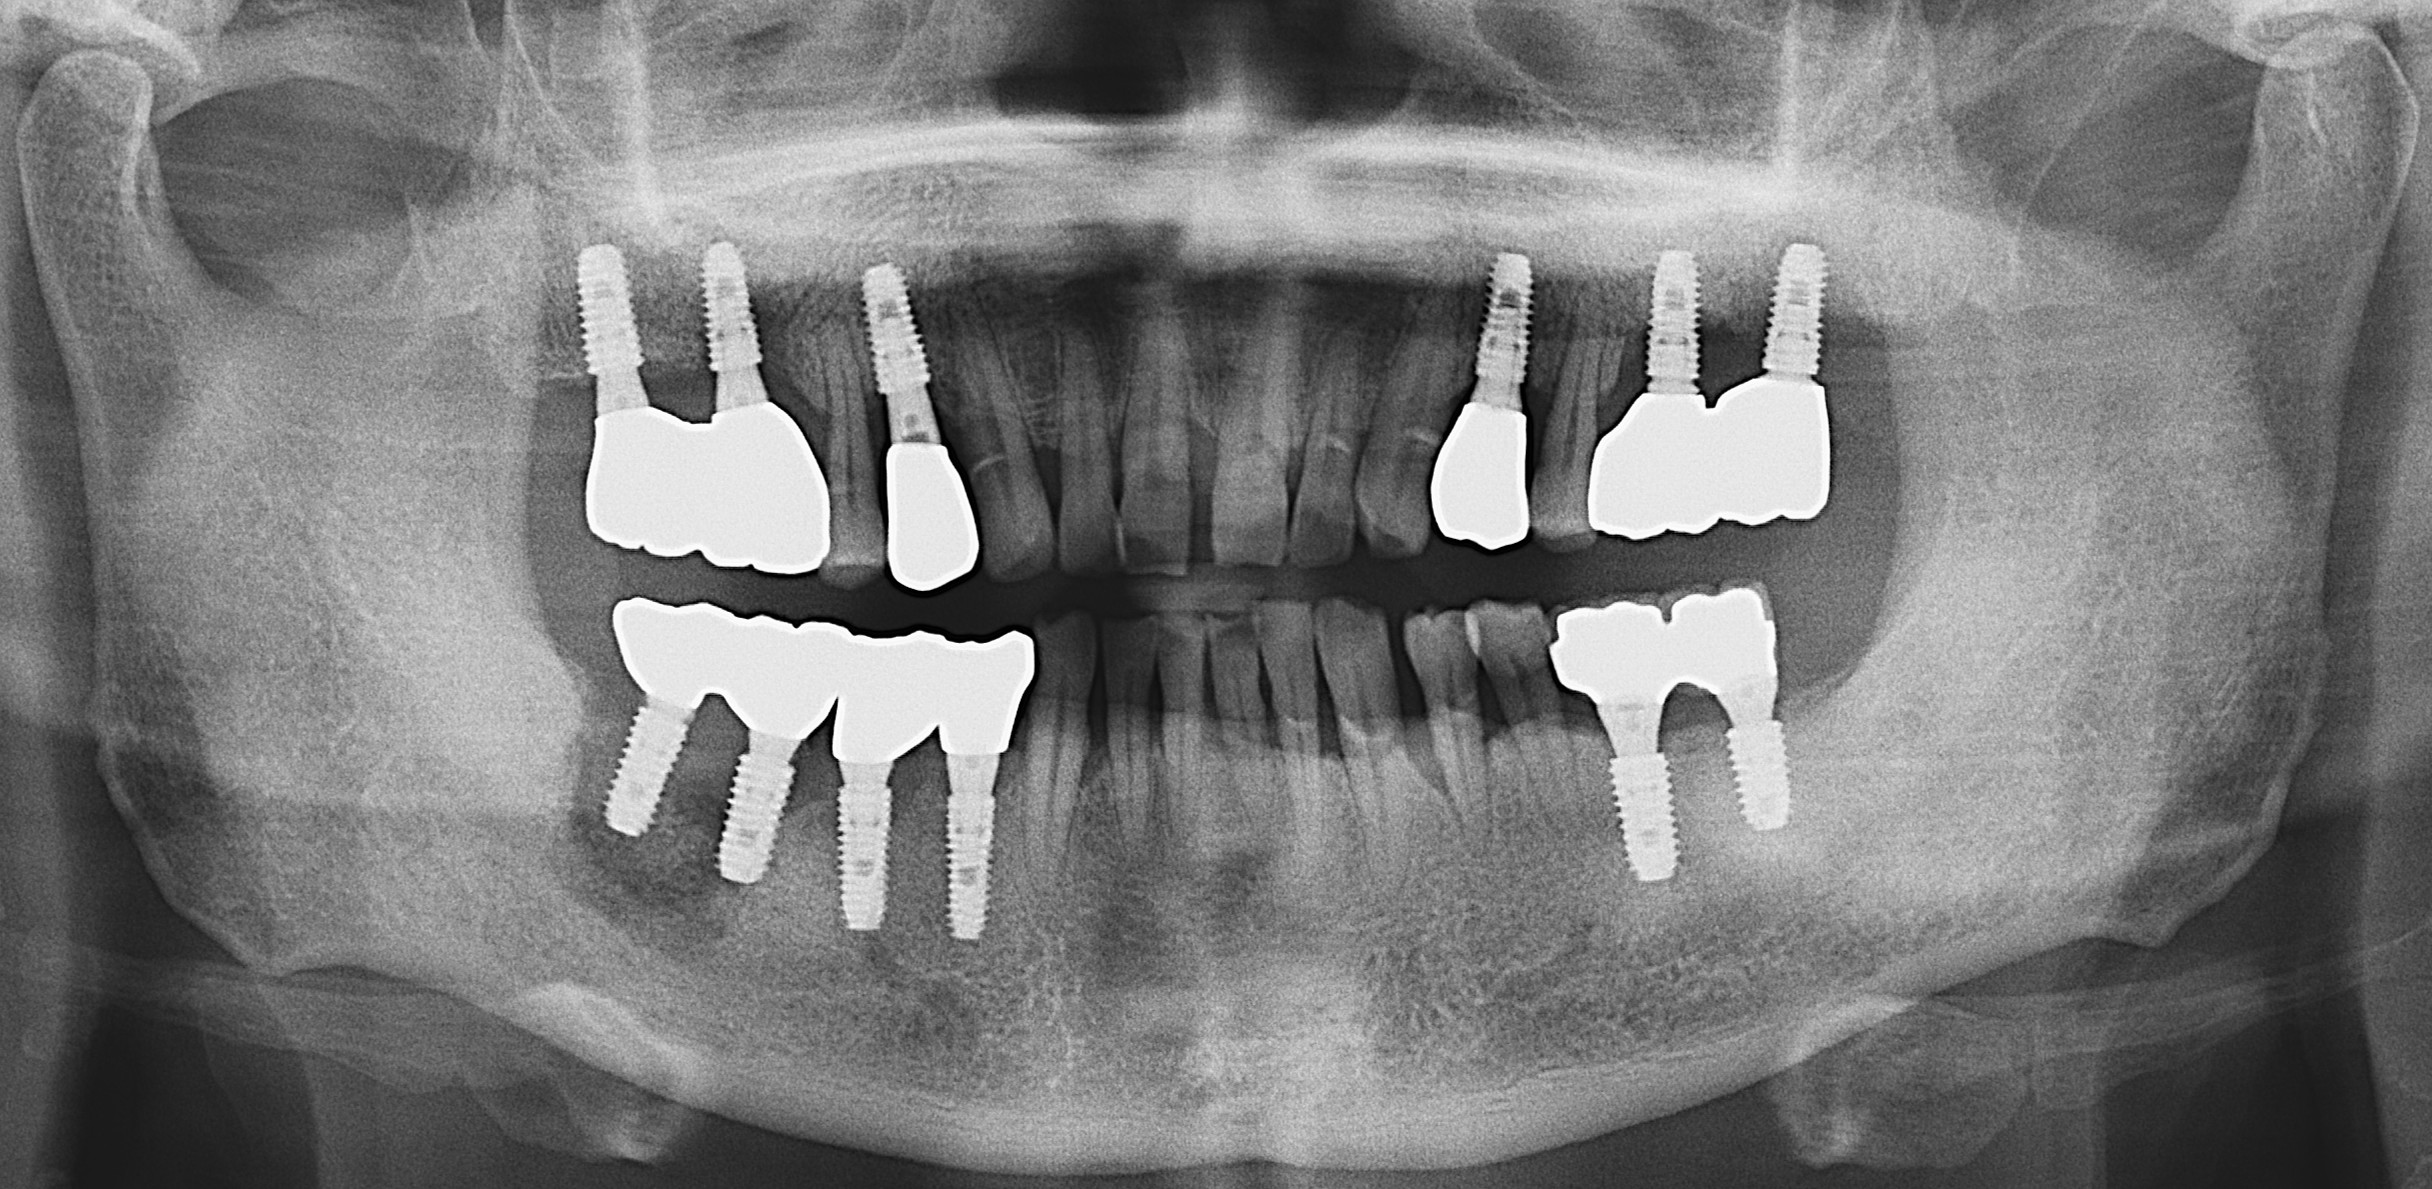

In 2016, dental implants were placed in Areas 47, 46, 45, and 44. In June, 2023, the patient experienced intermittent pain in these areas. Panoramic and other radiographic examinations revealed bone destruction around the implants (Fig. 1). In November 2023, implants i47 and 46 were removed at another institution.